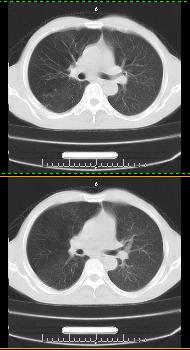

以下是引用liaoqiang在2008-3-21 17:45:00的发言:[br]右上叶尖段、后段有多发小结节和小条状影。考虑感染(结核可能性大。)。建议治疗后复查。

以下是引用王2008在2008-3-21 17:38:00的发言:[br]右上叶后段沿纹理走向呈串珠状.边缘欠清密度增高影,局部胸膜增厚.[br]考虑1.右上支扩可能.2.右上炎症.建议治疗后复查.请各位老师指教.

以下是引用lj11119999在2008-3-21 18:15:00的发言:[br]右上叶尖段、后段有多发小结节和小条状影。考虑感染(结核可能)建议进一步检查!